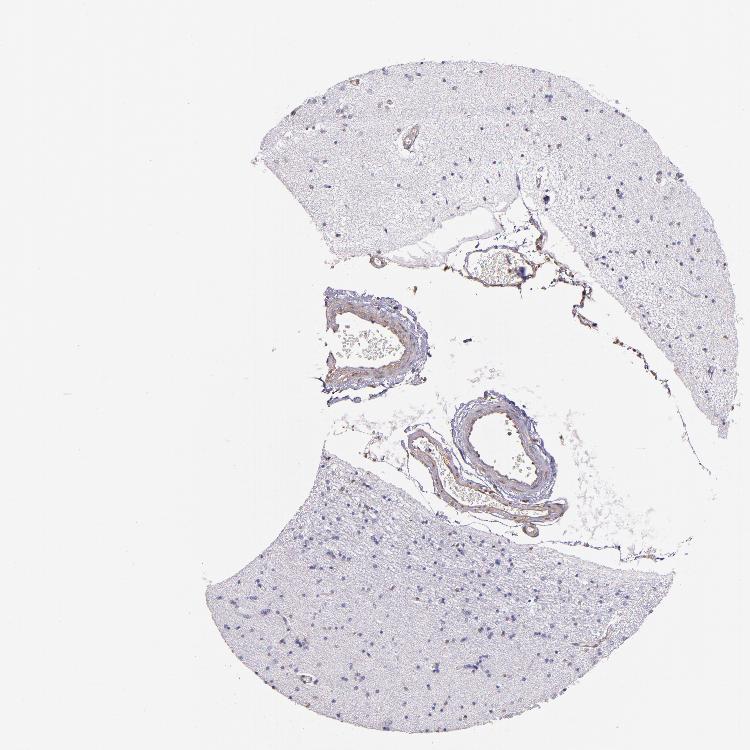

HIPPOCAMPUS - Antibody stainingi

Antibody staining in the annotated cell types in the current human tissue is reported as not detected, low, medium, or high, based on conventional immunohistochemistry profiling in selected tissues. This score is based on the combination of the staining intensity and fraction of stained cells.

Each image is clickable and will lead to virtual microscopy that enables deeper exploration of all samples and also displays staining intensity scores, fraction scores and subcellular localization as well as patient and tissue information for each sample.

Antibody HPA001861

Glial cells Not detected

Neuronal cells Not detected